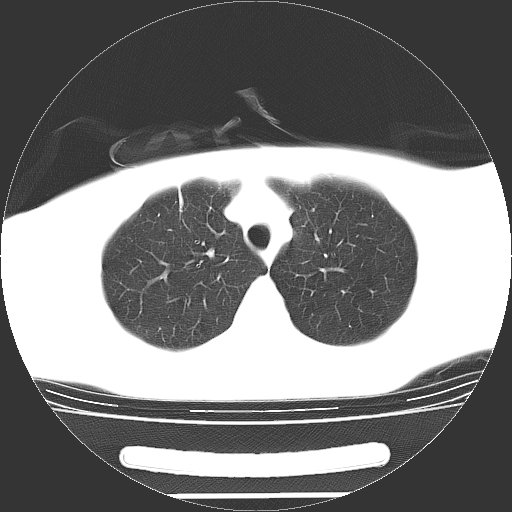

标题: CT19767:男,20岁,右侧气胸行闭式引流术后五天CT检查。 [打印本页]

男,20岁,右侧气胸行闭式引流术后五天ct检查看肺内是否有肺大泡,纵隔窗未见异常,未上传。

1)右侧胸腔闭式引流术后导管留置。2)右肺未见肺大泡。

未见肺大泡,还有微量气体。